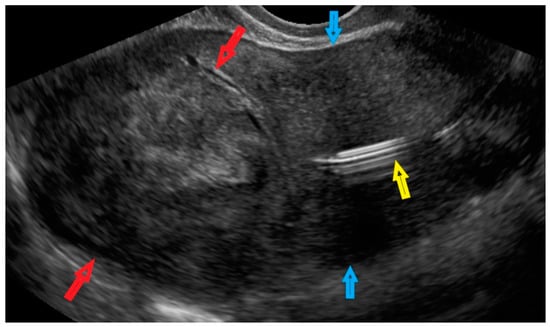

| 2 (36) | Sarcoma suspicion | Figure A2 | Yes | Tumorectomy, uterus preservation (young age) | LMS (UG-TUC core needle biopsy) | Yes | LMS | No | Yes |

| 3 (37) | Atypical uterine lesion | Figure A3 | Yes | No | Lipoleiomyoma (UG-TUC core needle biopsy) | No | - | Yes | Yes |

| 4 (56) | Atypical uterine lesion | Figure A4 | Yes | Yes | Leiomyoma (transvaginal ultrasound guided core needle biopsy) | Yes | Leiomyoma and adenomyosis | Yes | No |

| 5 (50) | Atypical uterine lesion (metastatic adenocarcinoma G3 in inguinal lymph node) | Figure A5 | Yes | No | Leiomyoma (UG-TUC core needle biopsy) | No | Uterus / tumor not resected because primary urological carcinoma was diagnosed | Yes | Yes |

| 6 (38) | Atypical uterine lesion | Figure A6 | Yes | No | Leiomyoma, epithelioid variant (UG-TUC core needle biopsy) | Yes (lesion enlarged during follow-up) | Leiomyoma, epithelioid variant | Yes | Yes |

| 7 (29) | Atypical uterine lesion | Figure A7 | Yes | Yes | Leiomyoma (UG-TUC core needle biopsy) | Yes | Leiomyoma with signs of degenerations | Yes | Yes |